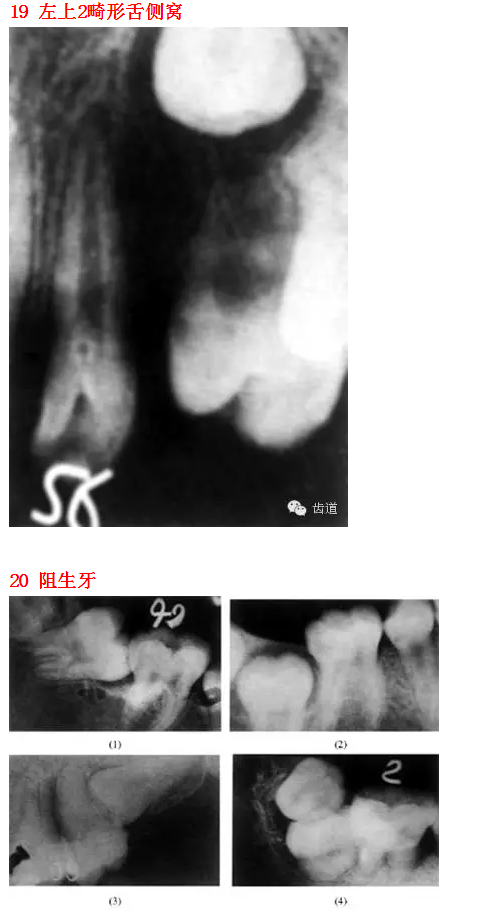

26種口腔病變X光片